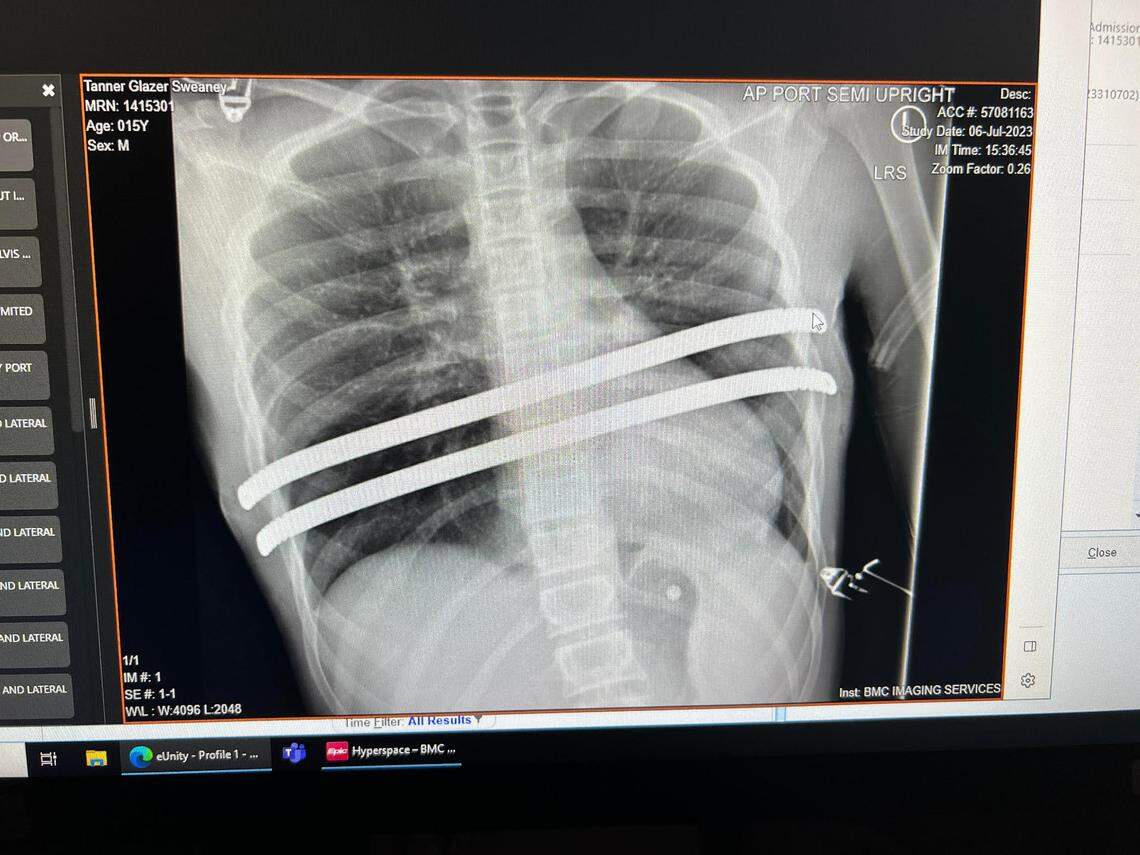

An ultrasound revealed that Tanner had a collapsed lung, and that the progression of his condition as he matured had caused his heart to be displaced. Surgery was scheduled immediately for July 6, 2023, to place two metal rods in his chest.

An X-ray shows the metal rods inserted into the chest of Rocky Mountain basketball player Tanner Sweaney, who has a condition known as pectus excavatum.

An X-ray shows the metal rods inserted into the chest of Rocky Mountain basketball player Tanner Sweaney, who has a condition known as pectus excavatum. Courtesy Summer Sweaney

Tanner spent a week in the hospital after the surgery. His recovery took six months, and there was a significant period of time when he couldn’t even raise his arms above his shoulders. The bars are to remain in place for two years.